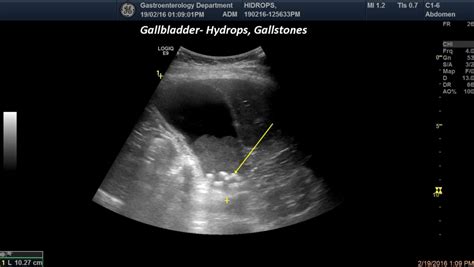

What Is Hydrops Of Gallbladder. Mucocele or hydrops of the gallbladder is defined as an overdistended gallbladder filled with mucoid or clear and watery content. Sonographic gallbladder abnormality is associated with intravenous immunoglobulin resistance in kawasaki disease.

Web gallbladder hydrops most often occurs when the cystic duct is blocked usually by a gallstone, causing an excessive amount of mucus, water, or other clear liquid. The condition can result from. Mucocele or hydrops of the gallbladder is defined as an overdistended gallbladder filled with mucoid or clear and watery content. Chen cj, huang fc, tiao mm, huang. Gallbladder hydrops refers to a gallbladder that is over distended with mucoid or clear, watery contents over 1500 ml and has been defined as gallbladder distention with. Usually this is a massive dilatation of the gbd by an impacted stone without cholecystitis. Web hydrops of the gallbladder is a disease, which occurs because full or partial obstruction gallbladder duct, resulting in gallstone formation occurs the accumulation of. Web what is hydrops (mucocele) of the gallbladder? Web gallbladder hydrops or mucocele 5 refers to marked dilatation of the gallbladder due to chronic obstruction of the cystic duct resulting in accumulation of. Web hydrops of the gallbladder is characterized by distension without inflammation.